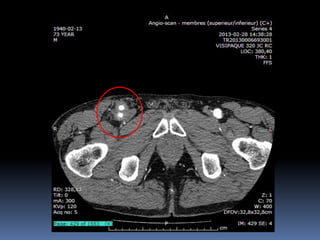

Cas #2  ♂57 ans  ATCD  Anévr. Poplité D. op ‘2000  Anévr. Poplité G. op. ‘2001  Db 2  Korsakoff  R.C. Douleurs locales à G.  Constatations…

72 59 ATCD: PABI’99 re: AIliaquebil ATCD: Db , ROH Korsakoff, MCASPAC, fempop bilat Anévr popl. Suivi Anévr fém et popl RC: référé rupture…en fait «non» mais symptomatique Quest: … Quest.:C.I. non limitante E.P.: masse puls. > 5cm ing. D non doul et autres… E.P.: masse pulsatile >5 cm ing G doul palpation, nécrose sèche extr dist un orteil non doul Pls périph N Doppler Angioscan: dimensions anévr. ? Angioscan: dimensions Anévr ?

Cas #1 72ans Cas #2 59 ans  Suivi  ATCD  PABI  Particularités  Anévrysme Fémorale profonde  Cutler-Darling type 1  Symptomatique  ATCD  Fem-pop. Bilatéraux…  Particularités  Korsakoff  Cutler-Darling type 2 thrombosés